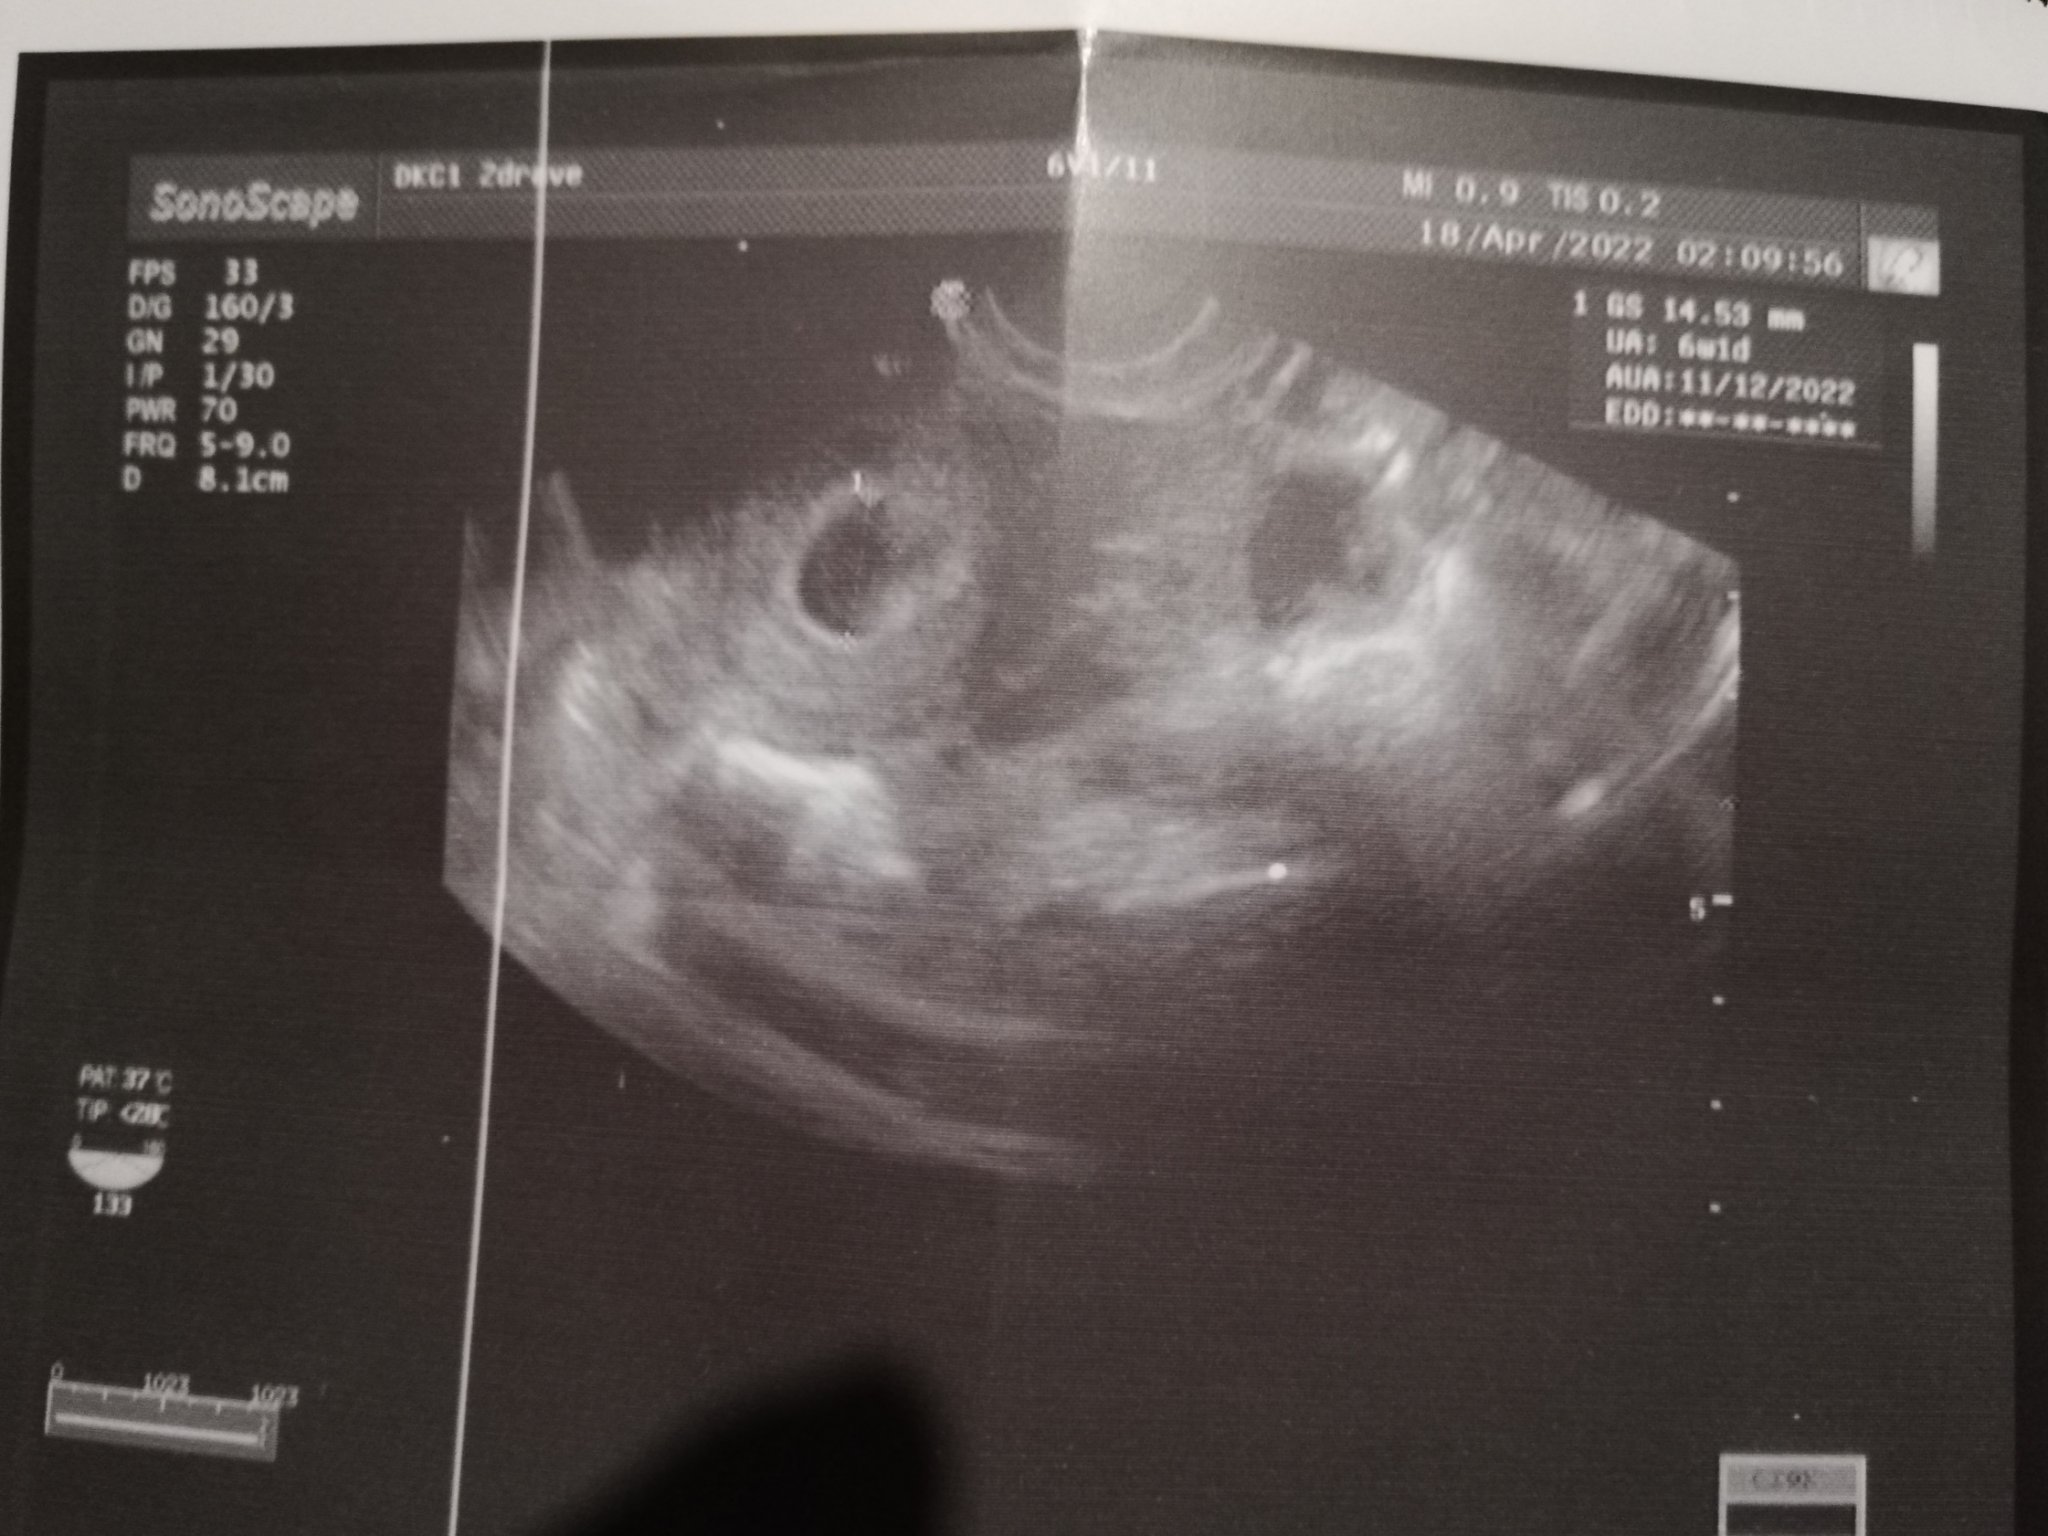

Здравейте, може ли да ми разчетете снимката. Днес бях на преглед със закъснение 10 дена  5г.с ми казаха.

Видя се плоден сак без ембрион, но докторката не каза нищо за жълтъчно мехурче, а от радост забравих да попитам. Благодаря предварително 🥰

Здравей, 5г.с. е още раничко. При мен в този период също се видя просто точка и дори доктора каза нека не констатираме бременност ела пак след 10 дни.